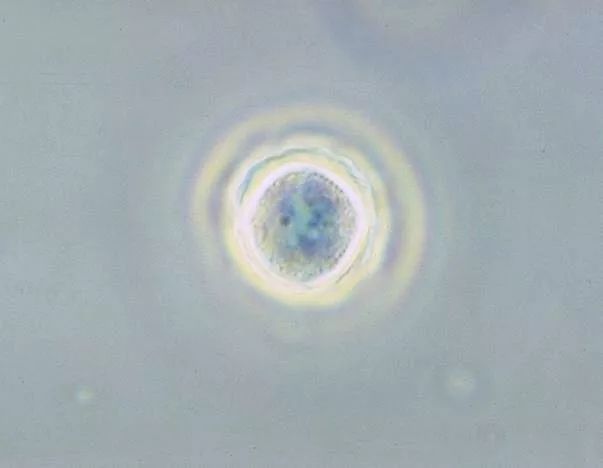

处在囊肿状态下的棘阿米巴原虫